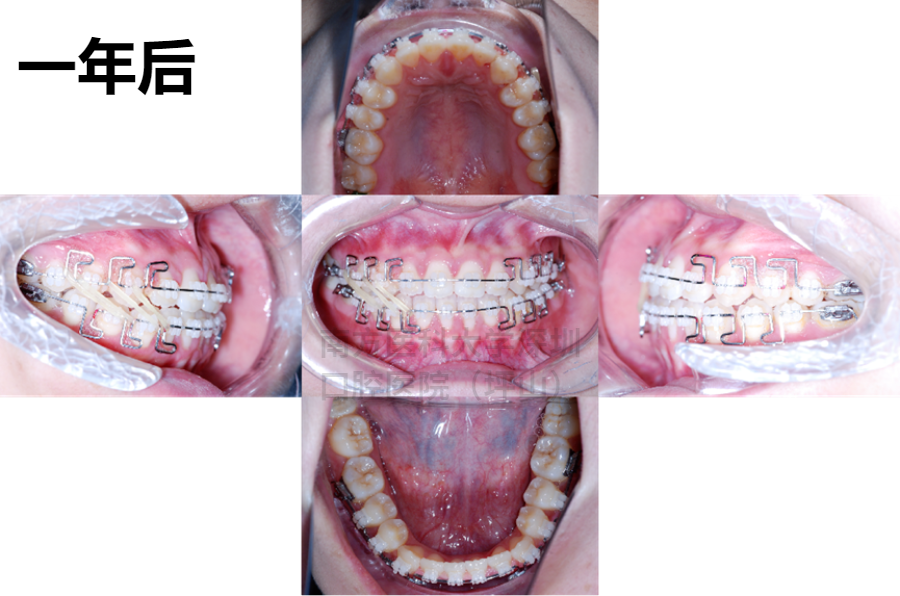

易医生决定,给我采用了一种叫做“妙弓”(MEAW)的技术进行矫正。

她说,妙弓是一种魔术般的矫正技术,经常用在重度开𬌗患者的矫治,我的情况也很合适,可以达到不错的矫治效果。

“需要哪个牙往哪个方向走,可以精准移动你的牙齿,”易医生说,妙弓技术很考验医生弯置的基本功,以及治疗方案的设计是否优秀。

易医生说,这种矫正方式有很多优点,它采用的是L形弯曲的方法,弓丝弹性好,作用力柔和,不压迫牙龈,也不用磨牙,可以精准调整我的咬合关系,不需要做手术,就可以纠正功能性的偏颌。